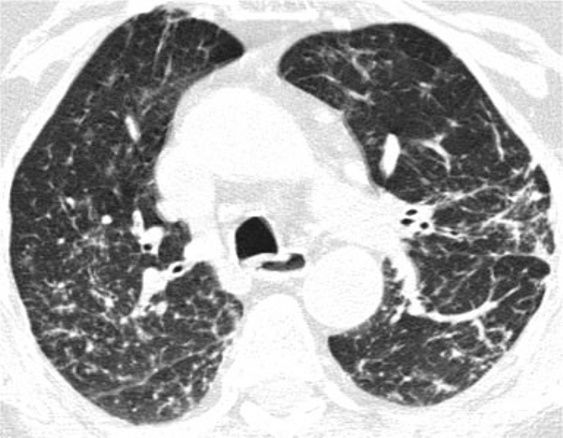

5、磨玻璃影-网状影混杂模式

有时,在肺部同一区域中可能同时存在磨玻璃样影和网状影共存,这种组合几乎等同于不可逆的纤维化。典型疾病:是非特异性间质性肺炎(NSIP)。表现为磨玻璃影改变为主、轻度网状改变。鉴别疾病:硬皮病、特发性肺纤维化(IPF)和脱屑性间质性肺炎(DIP)。

硬皮病的肺部侵袭类似于NSIP,因为它是最常见的组织学类型的纤维化。有利于硬皮病的主要发现是食管扩张和肺动脉扩张。

*硬皮病。下叶水平的HRCT表现为混合的“磨玻璃样和网状样”,其特征是磨玻璃样改变和牵引性支气管扩张。请注意5 mm胸膜下不受累,这是硬皮病最常见的组织学类型NSIP的特征相关性肺纤维化。

特发性肺纤维化(IPF)有时可能与NSIP难以区分,HRCT在区分IPF和NSIP方面的特异性范围为63%至70%。有利于IPF的鉴别诊断是呈现显著的网状蜂窝样改变,少许毛玻璃改变。

*IPF HRCT在肺底水平上表现出混合的“磨玻璃样和网状图案”,其特征是磨玻璃样改变的区域内可见牵引性支气管扩张和支气管扩张。少许蜂窝样改变。

单纯的脱皮性间质性肺炎(DIP)是罕见的,但其最常见的模式是磨玻璃样改变伴有轻度网状改变,能类似于NSIP,通常没有蜂窝状改变(图22)。可能有助于鉴别诊断的细微CT特征是存在可能代表肺气肿的小微囊肿(因为患者几乎总是吸烟者),支气管扩张或肺泡管扩张(无明显的蜂窝状纤维化)。

*DIP 患者HRCT的下叶水平显示出混合的“磨玻璃样改变伴轻度网状结构”。无蜂窝样改变